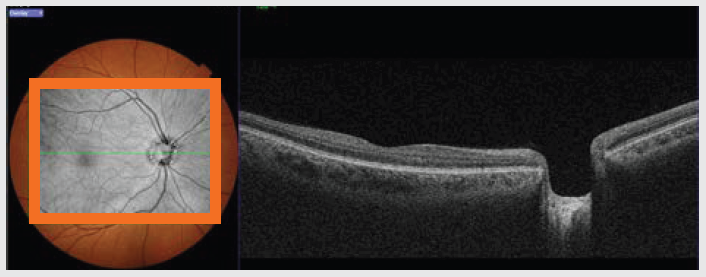

ANTERIOR SEGMENT